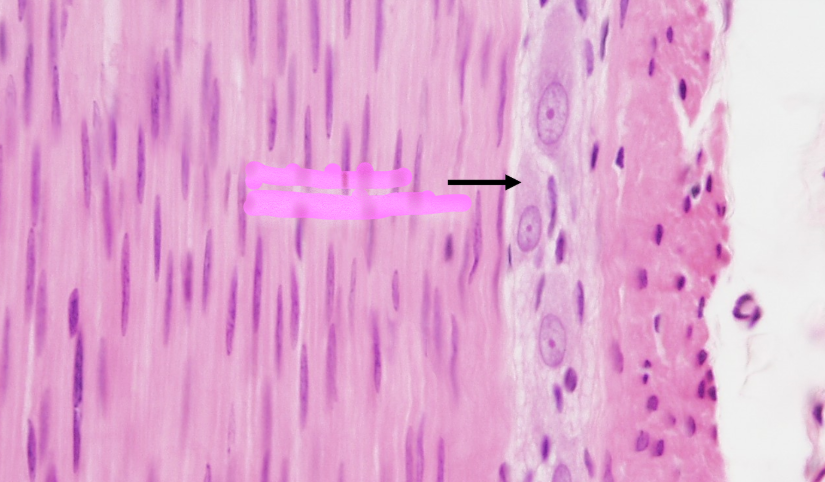

GC

ganglionic cells

Sub

Submucosa

MP

Meissner’s plexus

M(c)

muscularis